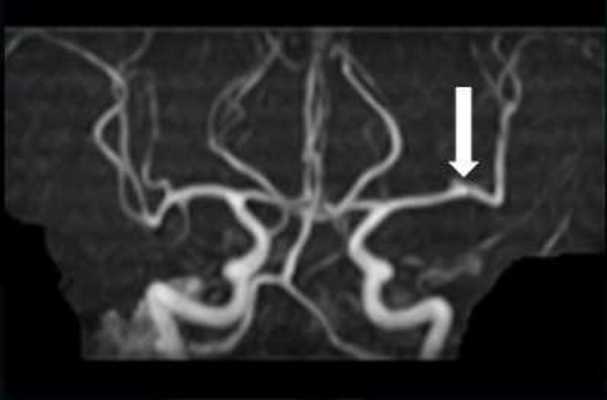

整形外科医今泉佳宣氏皆さんはモートン病という病気をご存じでしょうか。1876年にトーマス・モートン医師によって初めて報告された疾患です。足の裏の主に3番目と4番目の指(足趾(そくし))の間の付け...